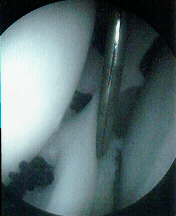

Diagnostic Arthroscopy- Indications

- Persistent pain and instability

- Recurrent effusions

- Obvious ACL injury or meniscal tear by clinical exam